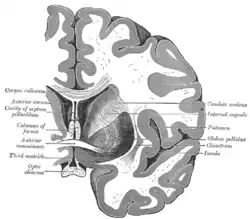

Transverse Cut of Brain (Horizontal Section), basal ganglia is blue | |

Together with the putamen, the caudate forms the dorsal striatum, which is considered a single functional structure; anatomically, it is separated by a large white matter tract, the internal capsule, so it is sometimes also referred to as two structures: the medial dorsal striatum (the caudate) and the lateral dorsal striatum (the putamen). In this vein, the two are functionally distinct not as a result of structural differences, but merely due to the topographical distribution of function.